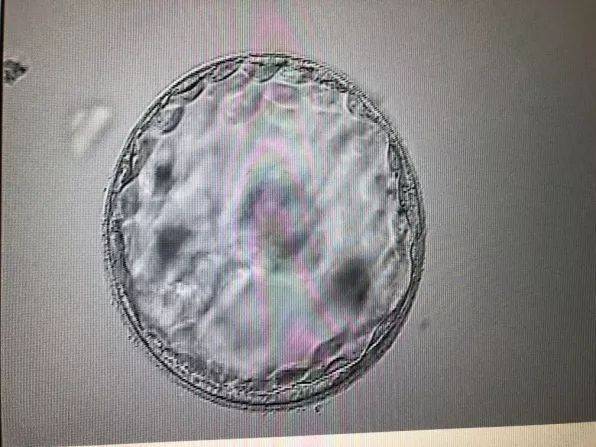

第三代试管婴儿技术,也称为胚胎植入前遗传学诊断/筛查(PGD/PGS),是一种在胚胎植入子宫前对其进行遗传物质分析的技术。这项技术可以帮助医生选择健康的胚胎进行移植,从而提高试管婴儿的成功率,并降低胎儿出生缺陷的风险。